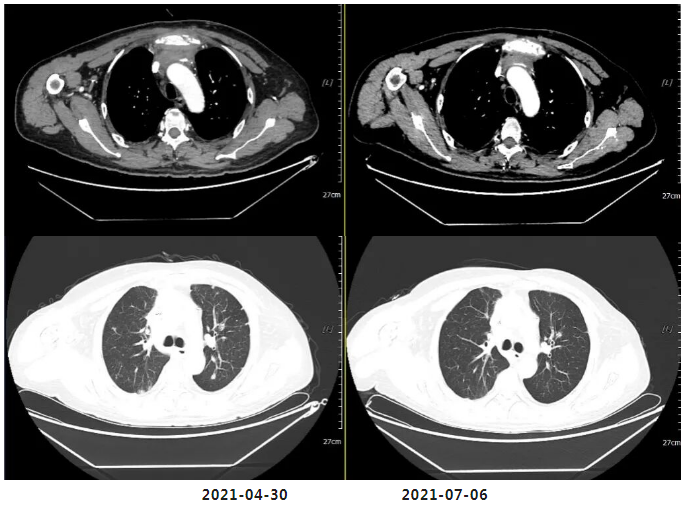

(四周期化疗后)复查疗效评价:SD(两肺及胸膜结节减少缩小;纵隔前间隙、纵隔内及两肺门淋巴结(2.5×3.0cm)较前部分缩小。